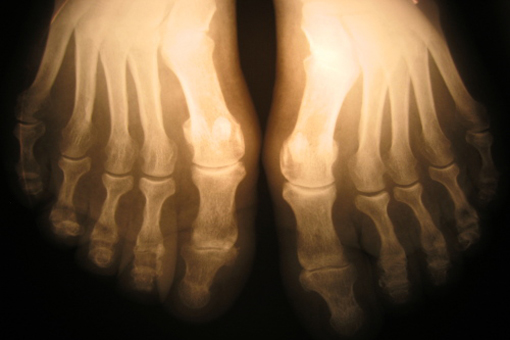

In pazienti affetti da artrite reumatoide (AR), la presenza di un maggior numero di articolazioni dolenti anziché tumefatte si lega ad outcome funzionali peggiori. Queste le conclusioni di uno studio pubblicato su ACR Open Rheumatology, che suggerisce che l’impiego della differenza tra la conta articolare delle articolazioni dolenti e quella delle articolazioni tumefatte potrebbe rivelarsi utile nell’identificare i pazienti a rischio di outcome funzionali peggiori.

Lo studio ha incluso 547 pazienti (70% donne) con un’età media di 56 anni e una durata media della malattia pari a 5,3 mesi. All’arruolamento nello studio, il 52% dei pazienti (n=287) presentava una TSJD superiore a zero, indicativa della presenza di un numero maggiore di articolazioni dolenti anziché tumefatte. Le grandi articolazioni rappresentavano questa differenza nel 43% dei pazienti e le piccole articolazioni nel 34% dei pazienti.

A 12 mesi, la percentuale di pazienti con una TSJD positiva è diminuita dal 52% al 32%, con il 25% dei pazienti che, in corrispondenza di questo timepoint, presentava una TSJD delle piccole articolazioni superiore a 0 e il 15% una TSJD delle grandi articolazioni superiore a 0.